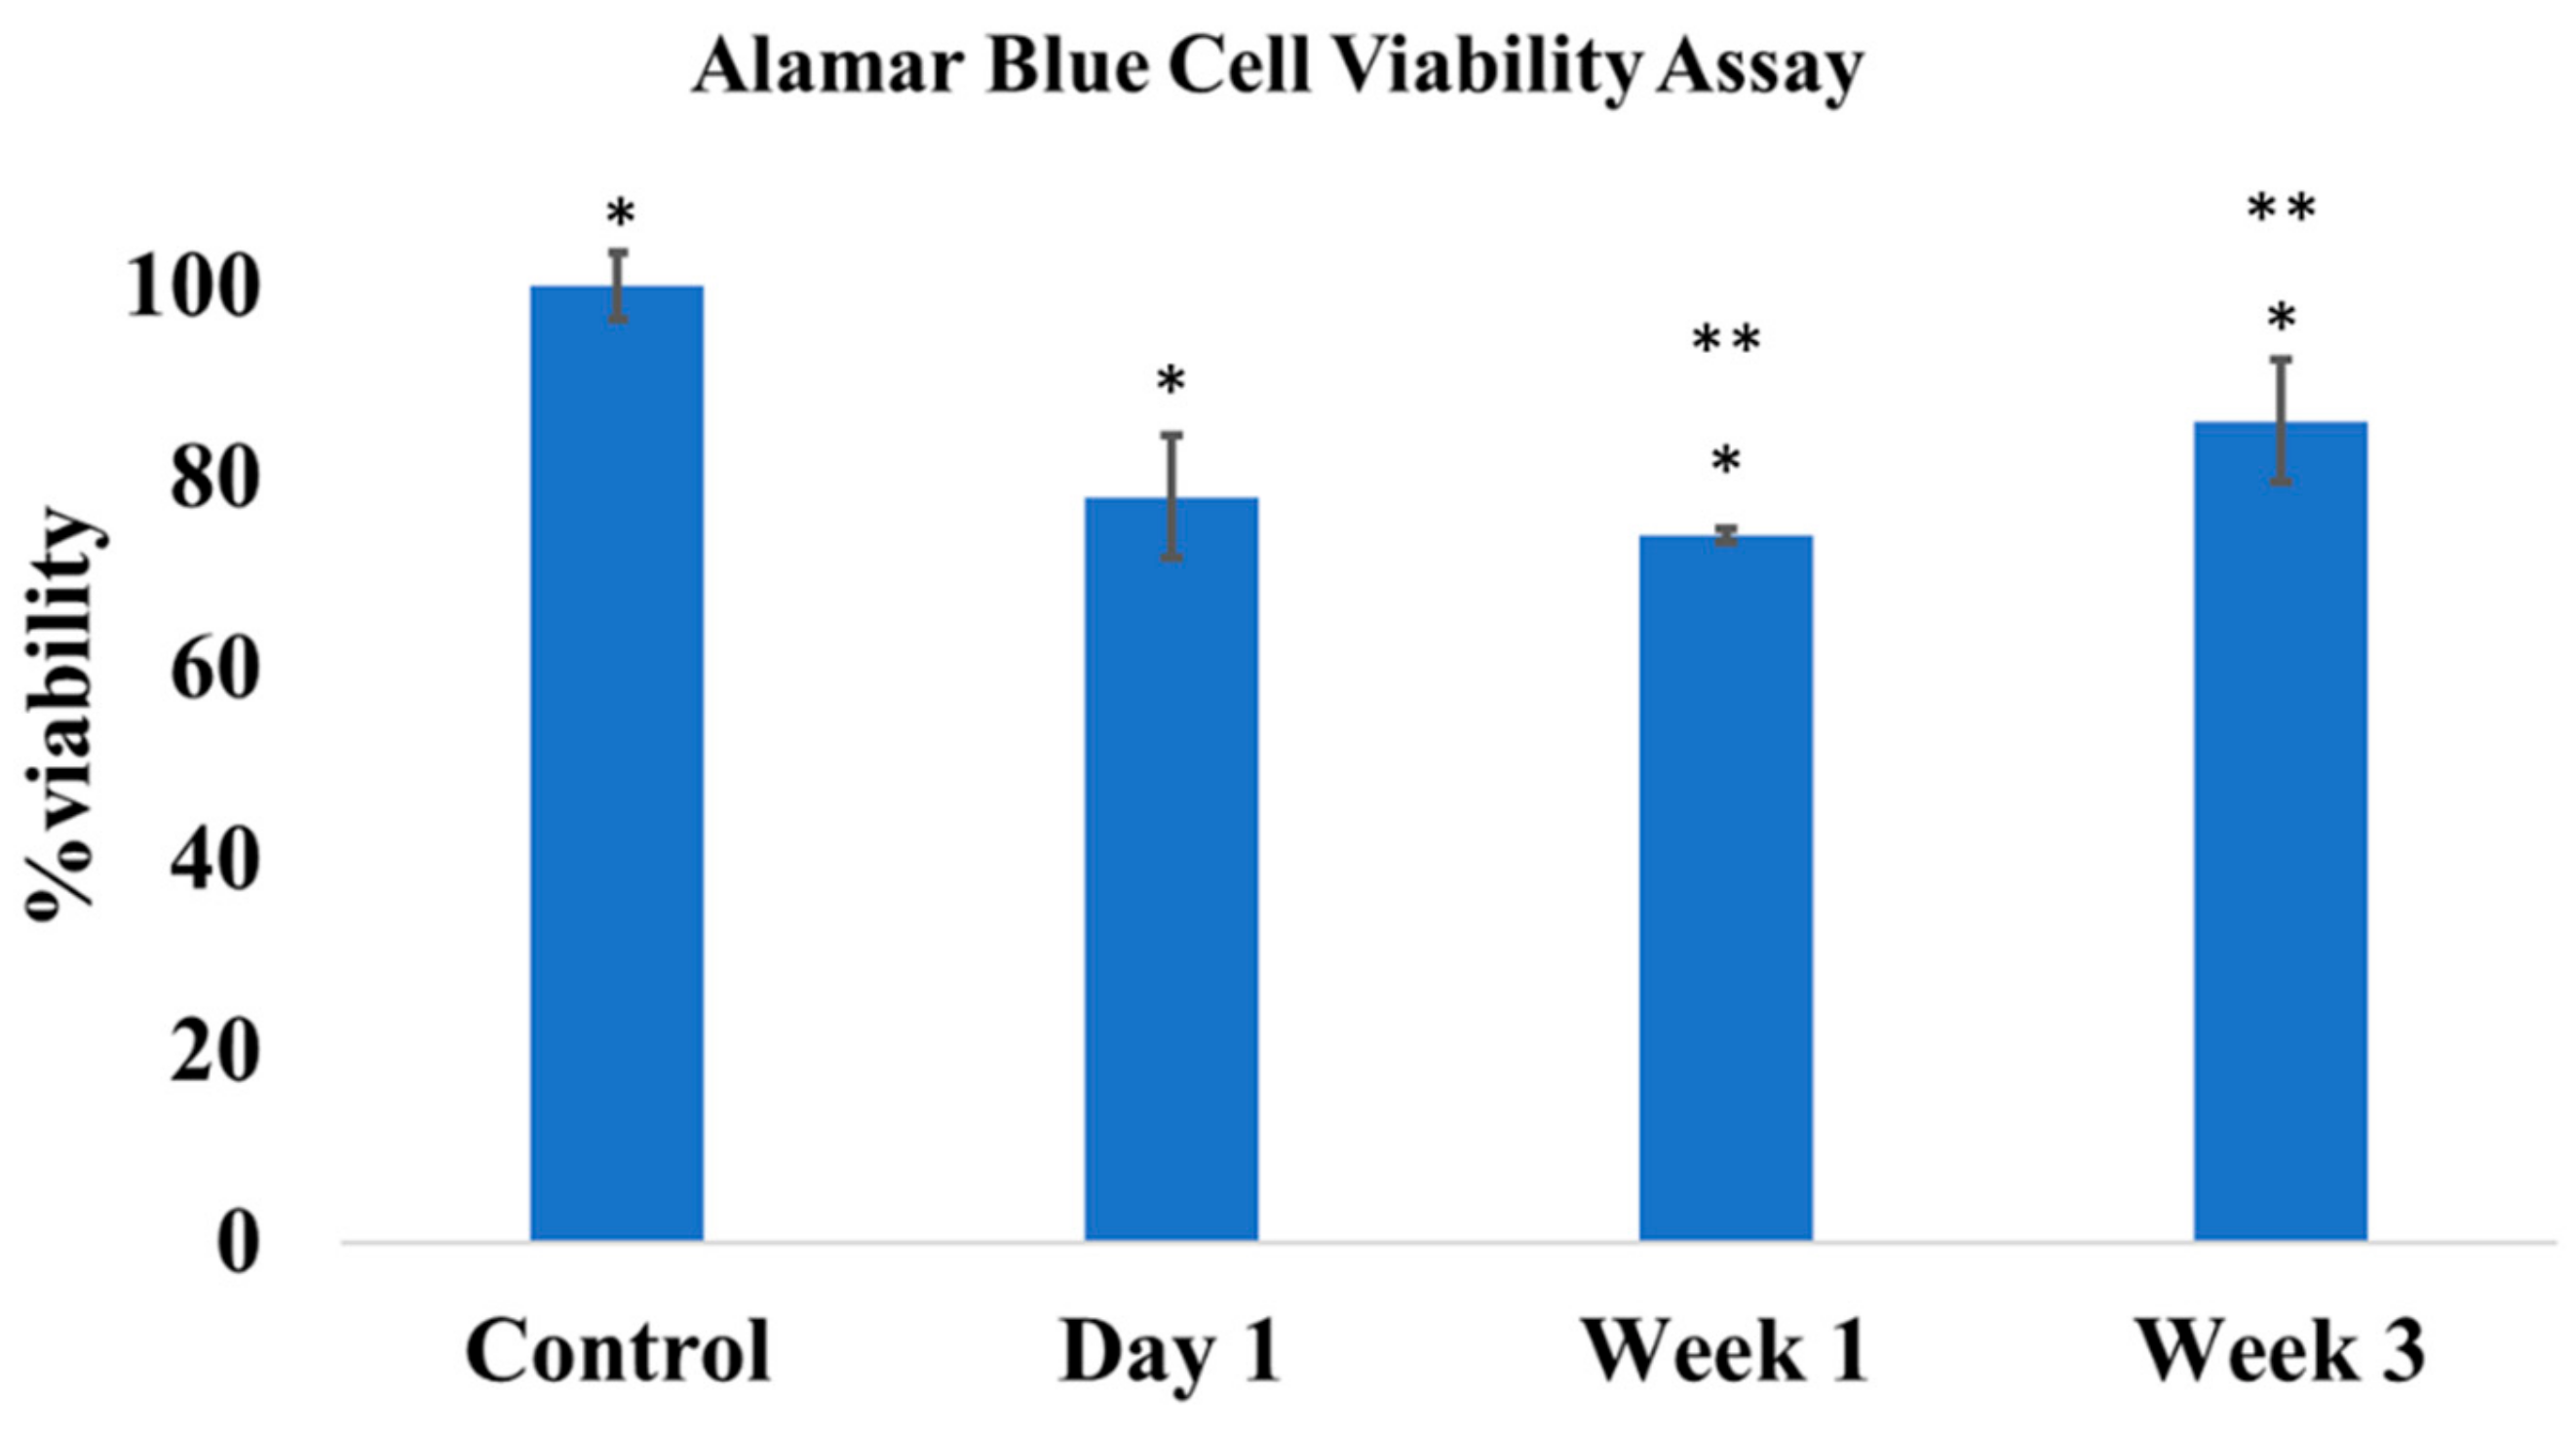

2.3.5. In Vitro Cytocompatibility

3.5. Rat Osteomyelitis Models

4. Discussion